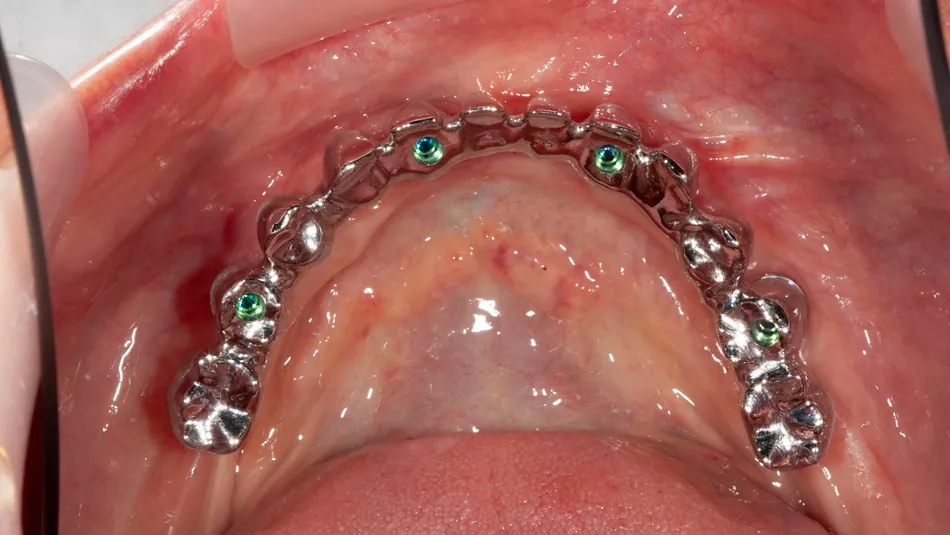

13. Occlusal pictures of healing around the implants at 3 months follow-up upon removal of the provisional prosthesis.